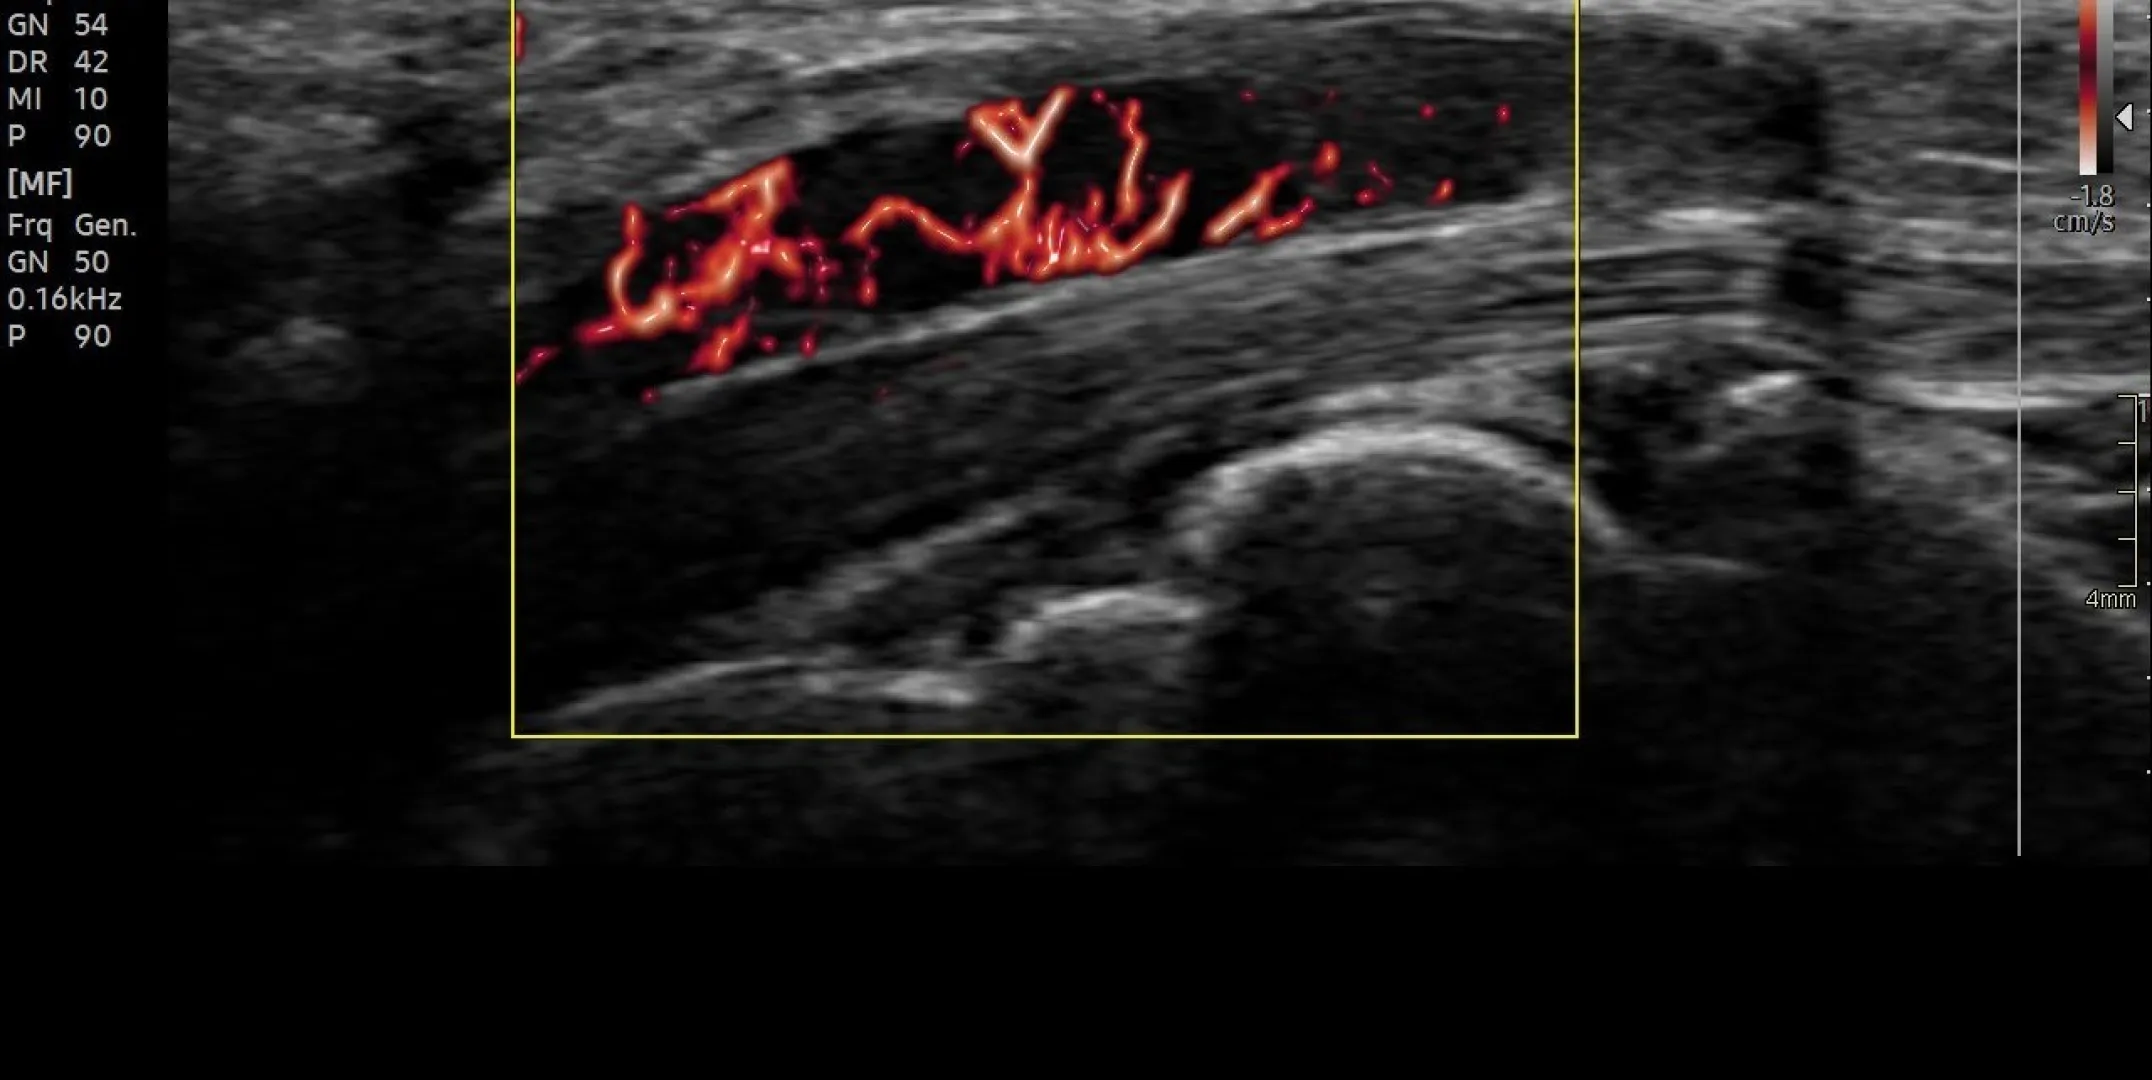

Milano, 13 maggio 2025 –Permette di visualizzare in tempo reale i tessuti molli, i tendini, le articolazioni e i vasi sanguigni, offrendo immagini ad alta risoluzione spesso paragonabili alla risonanza magnetica. Parliamo dell’ecografia: esame strumentale, indolore e non invasivo, che si avvale di ultrasuoni. Una metodica sempre più utilizzata nella chirurgia della mano perché supporta la diagnosi, guida le procedure chirurgiche, permette di valutare i risultati post-operatori ed è utile anche per stabilire il piano riabilitativo. “Gli ultrasuoni aiutano a identificare un’ampia gamma di problemi della mano, tra cui lesioni ai tendini, infiammazioni e alterazioni degenerative. Può anche essere utilizzata per individuare condizioni come il dito a scatto, la tenosinovite di De Quervain e la sindrome del tunnel carpale, in alcuni stati è diventato l’esame di primo livello nelle neuropatie compressive”, spiega il dott. Pierluigi Tos, Direttore della Chirurgia della Mano e Microchirurgia ricostruttiva ASST Gaetano Pini-CTO. “L’ecografia è uno strumento utile sia per la diagnostica sia per eseguire procedure mininvasive anche a livello ambulatoriale. Gli ultrasuoni sono inoltre indispensabili per eseguire iniezioni guidate per la gestione del dolore e il trattamento di varie patologie, quindi per le infiltrazioni o per esempio per gli scollamenti perinervosi, oppure è utile per guidare l’esecuzione di aspirati o biopsie” aggiunge il dott. Mauro Gallazzi, Direttore Radiodiagnostica ASST Gaetano Pini-CTO.

Il vantaggio maggiore nell’utilizzo dell’ecografia rispetto alla TAC, alla risonanza magnetica o alla radiografia, è che gli ultrasuoni possono essere utilizzati anche con l’arto in movimento. Questo consente al chirurgo di fare delle valutazioni sulla dinamica, condizione fondamentale per formulare delle diagnosi di patologie o lesioni che si evidenziano solo muovendo la mano come per esempio per la lesione della puleggia. “Nel dito – spiega il dott. Tos - le pulegge sono una serie di anelli che formano un tunnel attraverso il quale i tendini devono scorrere, ovvero il canale digitale. Possiamo immaginarlo come le guide su una canna da pesca attraverso cui deve passare la lenza. Al posto della lenza abbiamo il tendine. Lo scopo delle pulegge è tenere i tendini vicini all'osso durante lo scorrimento. Se avviene la lesione di una o più pulegge si verifica il cosiddetto effetto ‘corda d’arco’, ovvero il tendine si allontana dal piano osseo in maniera patologica”.

La collaborazione tra medici radiologi e medici chirurghi specializzati nella chirurgia della mano consente quindi di migliorare notevolmente sia la diagnosi sia la cura delle patologie della mano. L’ASST Gaetano Pini-CTO ha al suo interno un team multidisciplinare che lavora in stretta collaborazione in particolare per le patologie del sistema nervoso periferico: grazie al supporto dei medici radiologi, i chirurghi sono in grado di avere una diagnosi precoce e puntuale delle lesioni traumatiche oppure tumorali dei nervi periferici.